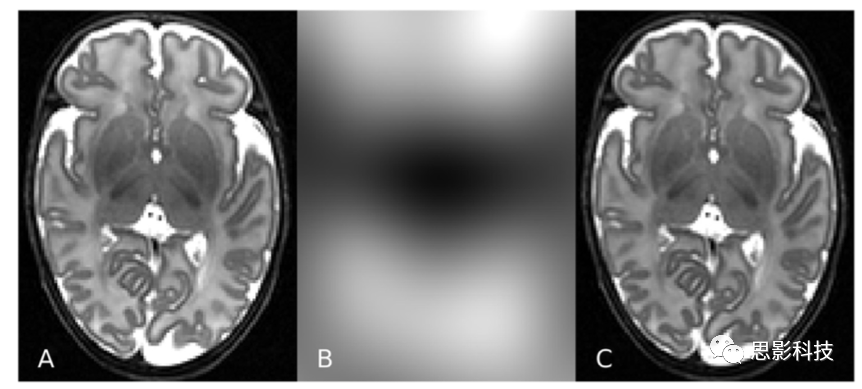

盡管在獲取磁共振圖像方面取得了一些進(jìn)展,但自動化的大腦分割仍然是一項艱巨的任務(wù)。在MR圖像中有一些重要的挑戰(zhàn),這些挑戰(zhàn)阻礙了分割,而與當(dāng)前的應(yīng)用無關(guān)。不同組織類別的強度不是均勻的,而是在圖像空間上逐漸變化的。這種強度非均勻性(INU)是由非單形射頻(RF)場和接收靈敏度以及與身體的電磁相互作用造成的。更高場強的掃描儀會導(dǎo)致更大的強度變化。圖1展示了INU效應(yīng)。在單個體素中混合不同組織類別的部分容積(PV)效應(yīng)給組織邊界的精確描繪帶來了額外的困難。由于圖像分辨率有限,包含多個組織的體素產(chǎn)生的強度表示體素中多種組織的混合強度。圖像噪聲經(jīng)常是比較明顯的,可能是由于人體中的電磁噪聲和接收電子設(shè)備中的小異常造成的。胎兒和新生兒腦MRI的自動分割比成人腦分割具有更大的挑戰(zhàn)性。圍產(chǎn)期腦MR圖像進(jìn)一步顯示了該領(lǐng)域特有的挑戰(zhàn):

1.新生兒T2 MR圖像上顯示的MRI強度不均勻性(A)。圖像(B)和(C)使用N4偏置場校正分別呈現(xiàn)估計的偏置場和偏置校正后的圖像。